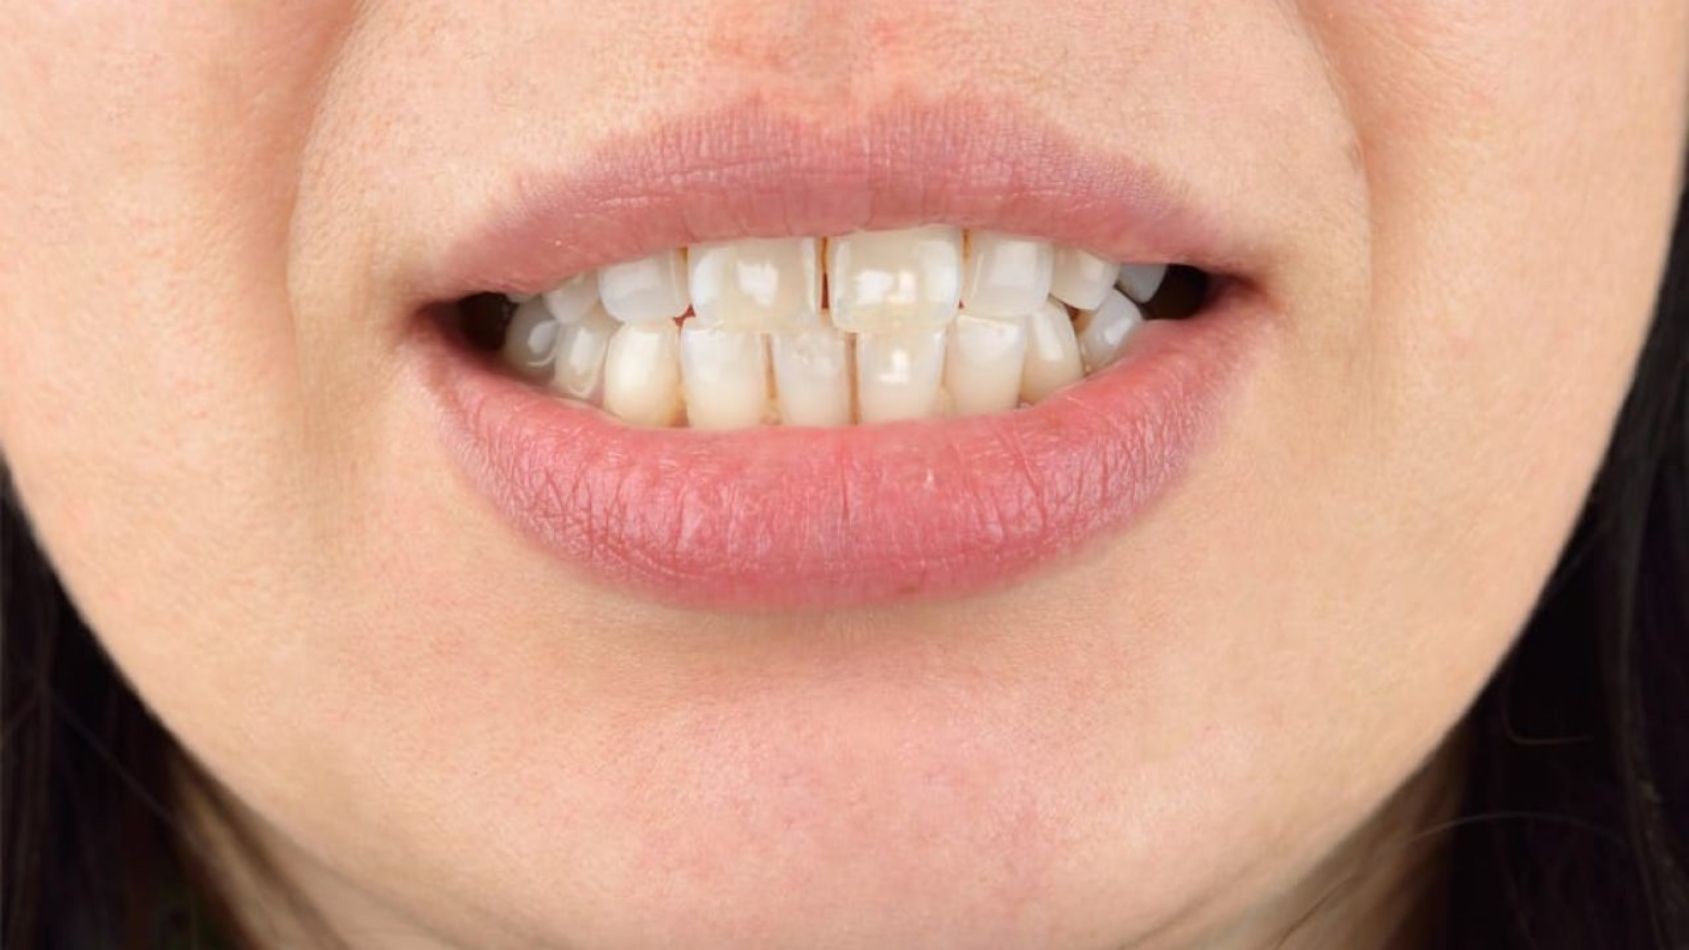

While low levels of fluoride help strengthen and protect tooth enamel, too much fluoride can cause dental fluorosis -- a discoloration of teeth, usually with opaque white marks, lines, or mottled enamel and poor mineralization. Dental fluorosis occurs when children between birth and around nine years of age are exposed to high levels fluoride during this critical window when their teeth are forming, and can actually increase their risk of tooth decay. A survey by the CDC found that roughly 25 percent of the U.S. population examined (ages 6 to 49) show some degree of dental fluorosis.